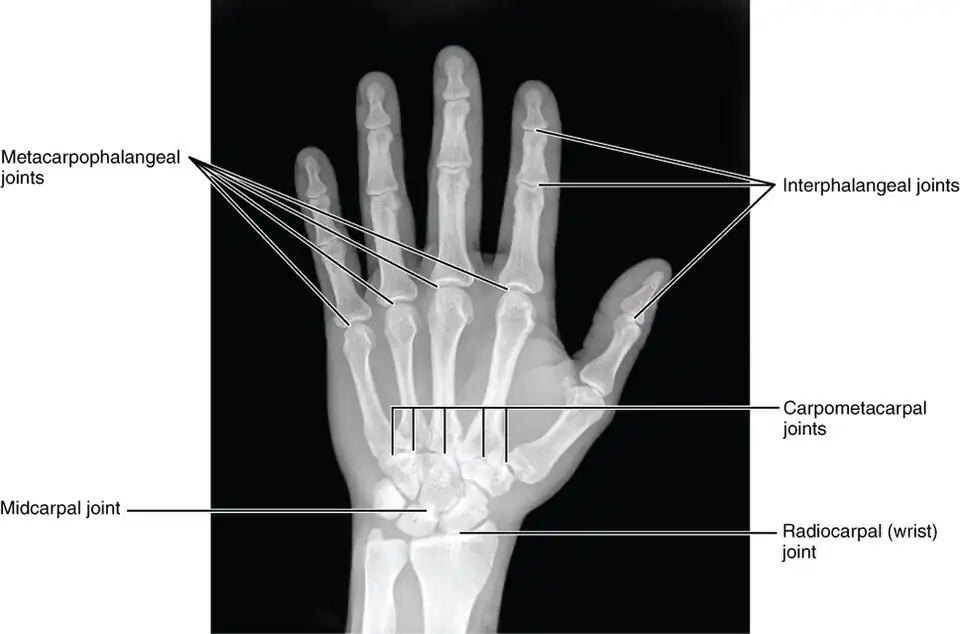

Carpometacarpal joints of the left hand. Thumb on left.

Carpometacarpal joints of the left hand. Thumb on left. -

Carpometacarpal joints of the left hand. Thumb on left.

Carpometacarpal joints of the left hand. Thumb on left. -

X-ray

X-ray

X-ray image of right hand with thumb on left.

X-ray image of right hand with thumb on left. -